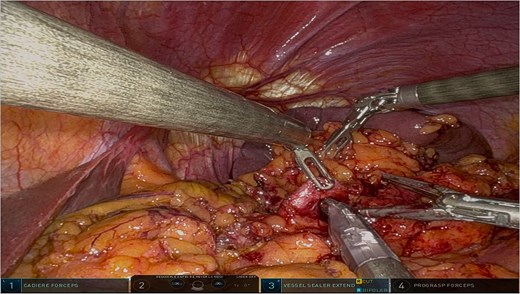

The surgery was performed using the Da Vinci robotic system under general anesthesia. The patient was positioned supine with reverse Trendelenburg. Four robotic trocars and one assistant trocar were placed. The gastro-splenic ligament was dissected to expose the distal pancreas, and the pancreas was transected using a linear stapler, ensuring tumor-free margins (Fig. 2). The splenic artery and vein were individually ligated with robotic sutures, and the spleen was mobilized and removed along with the pancreas (Fig. 3). The specimen was extracted via mini-laparotomy and sent for histopathological analysis (Fig. 4).

Complete surgical specimen, including the distal pancreas and spleen, shown after extraction via a mini-laparotomy. The specimen demonstrates clear resection margins, achieved through robotic precision, highlighting the effectiveness of the surgical approach.